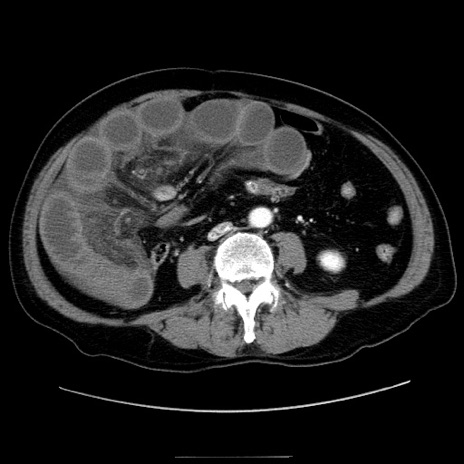

症例30(横断像)

【症例】80歳代男性

【主訴】臍周囲痛

【現病歴】約6時間前から臍下部痛が出現。次第に腹部膨隆・背部痛も生じてきたため来院。背部痛の場所は変化しない。

【身体所見】意識清明、BT 36.3℃、BP  131/87mmHg、P 87bpm、SpO2 100%(RA)、臍周囲自発痛・圧痛あり、反跳痛なし、自発痛部位に一致して板状硬あり、腹部膨隆、腸雑音減弱、CVA tenderness両側陰性。

【データ】WBC 19600、CRP 0.33